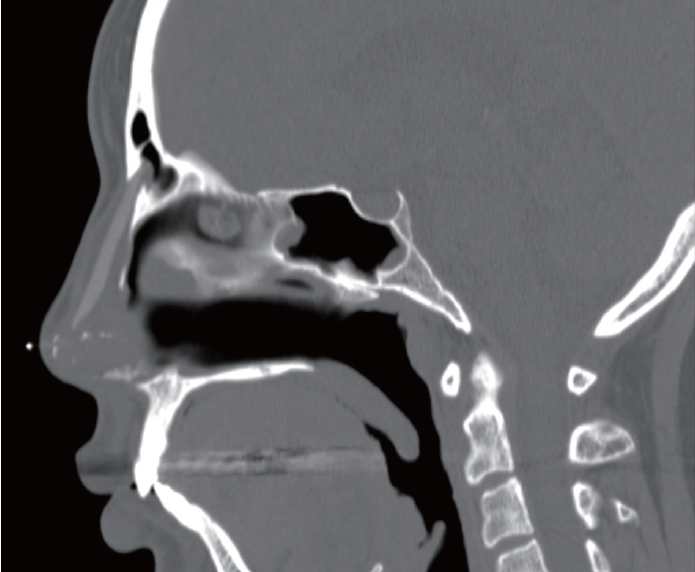

A CT scan revealed foreign body penetration of the anterior table of the frontal sinus without evidence of sinusitis (Fig. 2).

Fig. 2.Sagittal CT scan cut showed penetration of anterior table of frontal sinus by a foreign body implant for a rhinoplasty. Fig. 3.Intraoperative endoscopic findings of nasal bone and frontal sinus defects. A: Intraoperative endoscopic view of nasal dorsum showed left nasal bone defect and hole of anterior table of frontal sinus after removal of foreign body implant. B and C: Before debridement of granulation tissue in frontal sinus wall defect (B), after debridement (C). Fig. 4.Reconstruction process of the nasal bone and frontal sinus defects. A: The defects was reconstructed by placing homologous fascia, secured with fibrin glue. B: Ear cartilage har- vested from the right auricular cymba concha, was placed on top of the fascia to reinforce the reconstructed site. REFERENCES1. Winkler AA, Soler ZM, Leong PL, Murphy A, Wang TD, Cook TA. Complications associated with alloplastic implants in rhinoplasty. Arch Facial Plast Surg 2012;14(6):437-41.